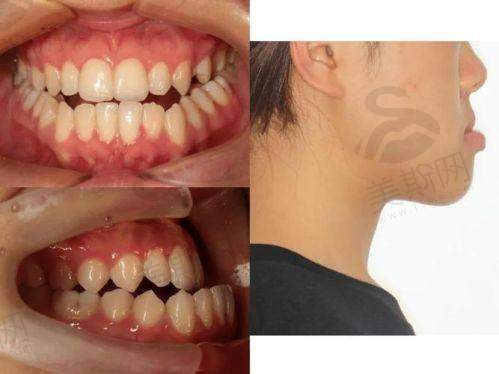

作为国内首批开展舌侧矫正的骨干医生,他研发的“个性化舌侧托槽系统”通过3D打印技术定制托槽角度,使矫治力作用点更接近牙阻抗中 心,在压前牙内收、上颌扩弓等方面成效提升40%。临床实例显示,骨性凸嘴患者采用舌侧矫正 + 颌位调整技术,18 - 24个月可实现侧貌从凸面型到直面型的转变,复发率低于2%。

实例1:骨性龅牙不拔牙矫正

28岁女性患者因“嘴凸明显、笑露牙龈”就诊,诊断为中度骨性龅牙(ANB角8°),传统方案需拔除4颗前磨牙。张栋梁医生采用“隐适美 + 微种植体支抗”方案,通过推磨牙向后创造间隙,配合负转矩控制技术内收前牙5mm,24个月矫正后侧貌从凸面型变为直面型,微笑线弧度自然,患者反馈:“原本以为必须手术,没想到不拔芽也能拥有明星侧颜!”